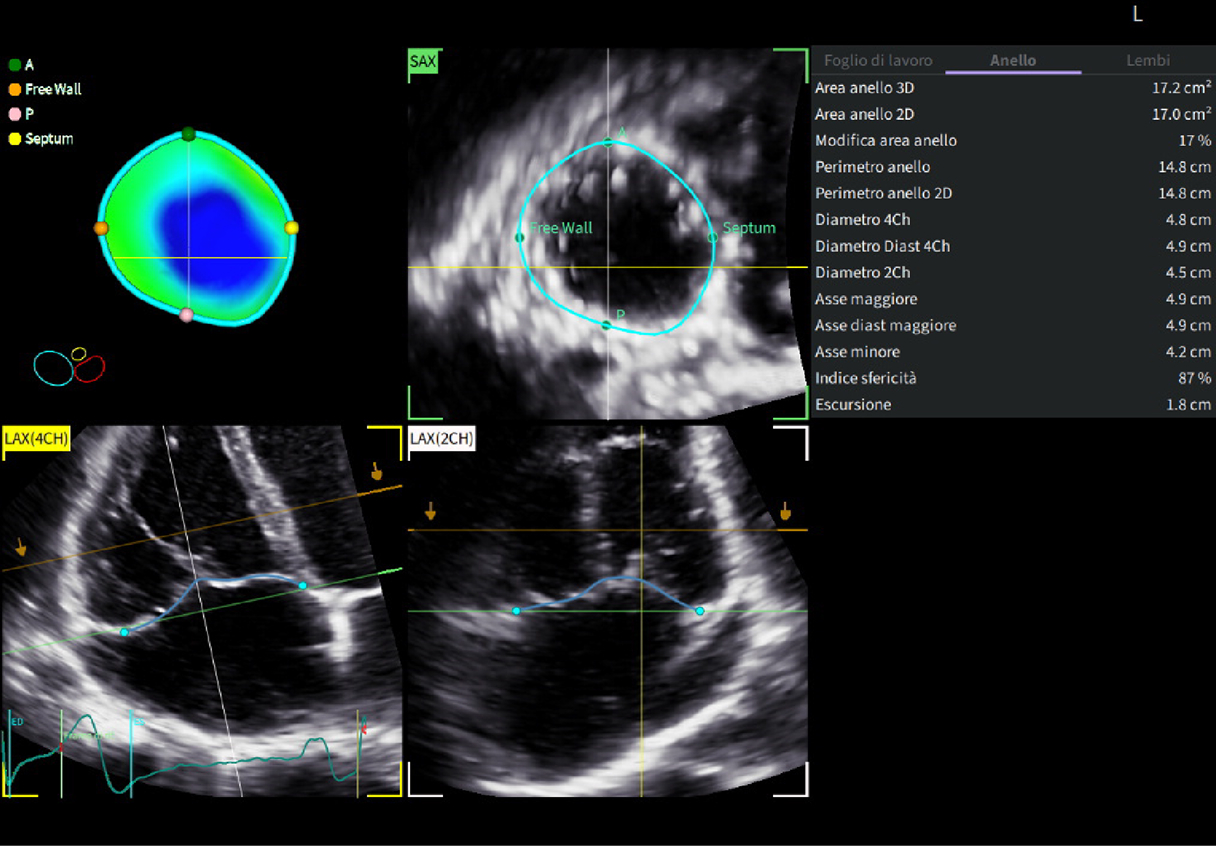

Fifty shades of grey

Caso condiviso da Marcello De Santis